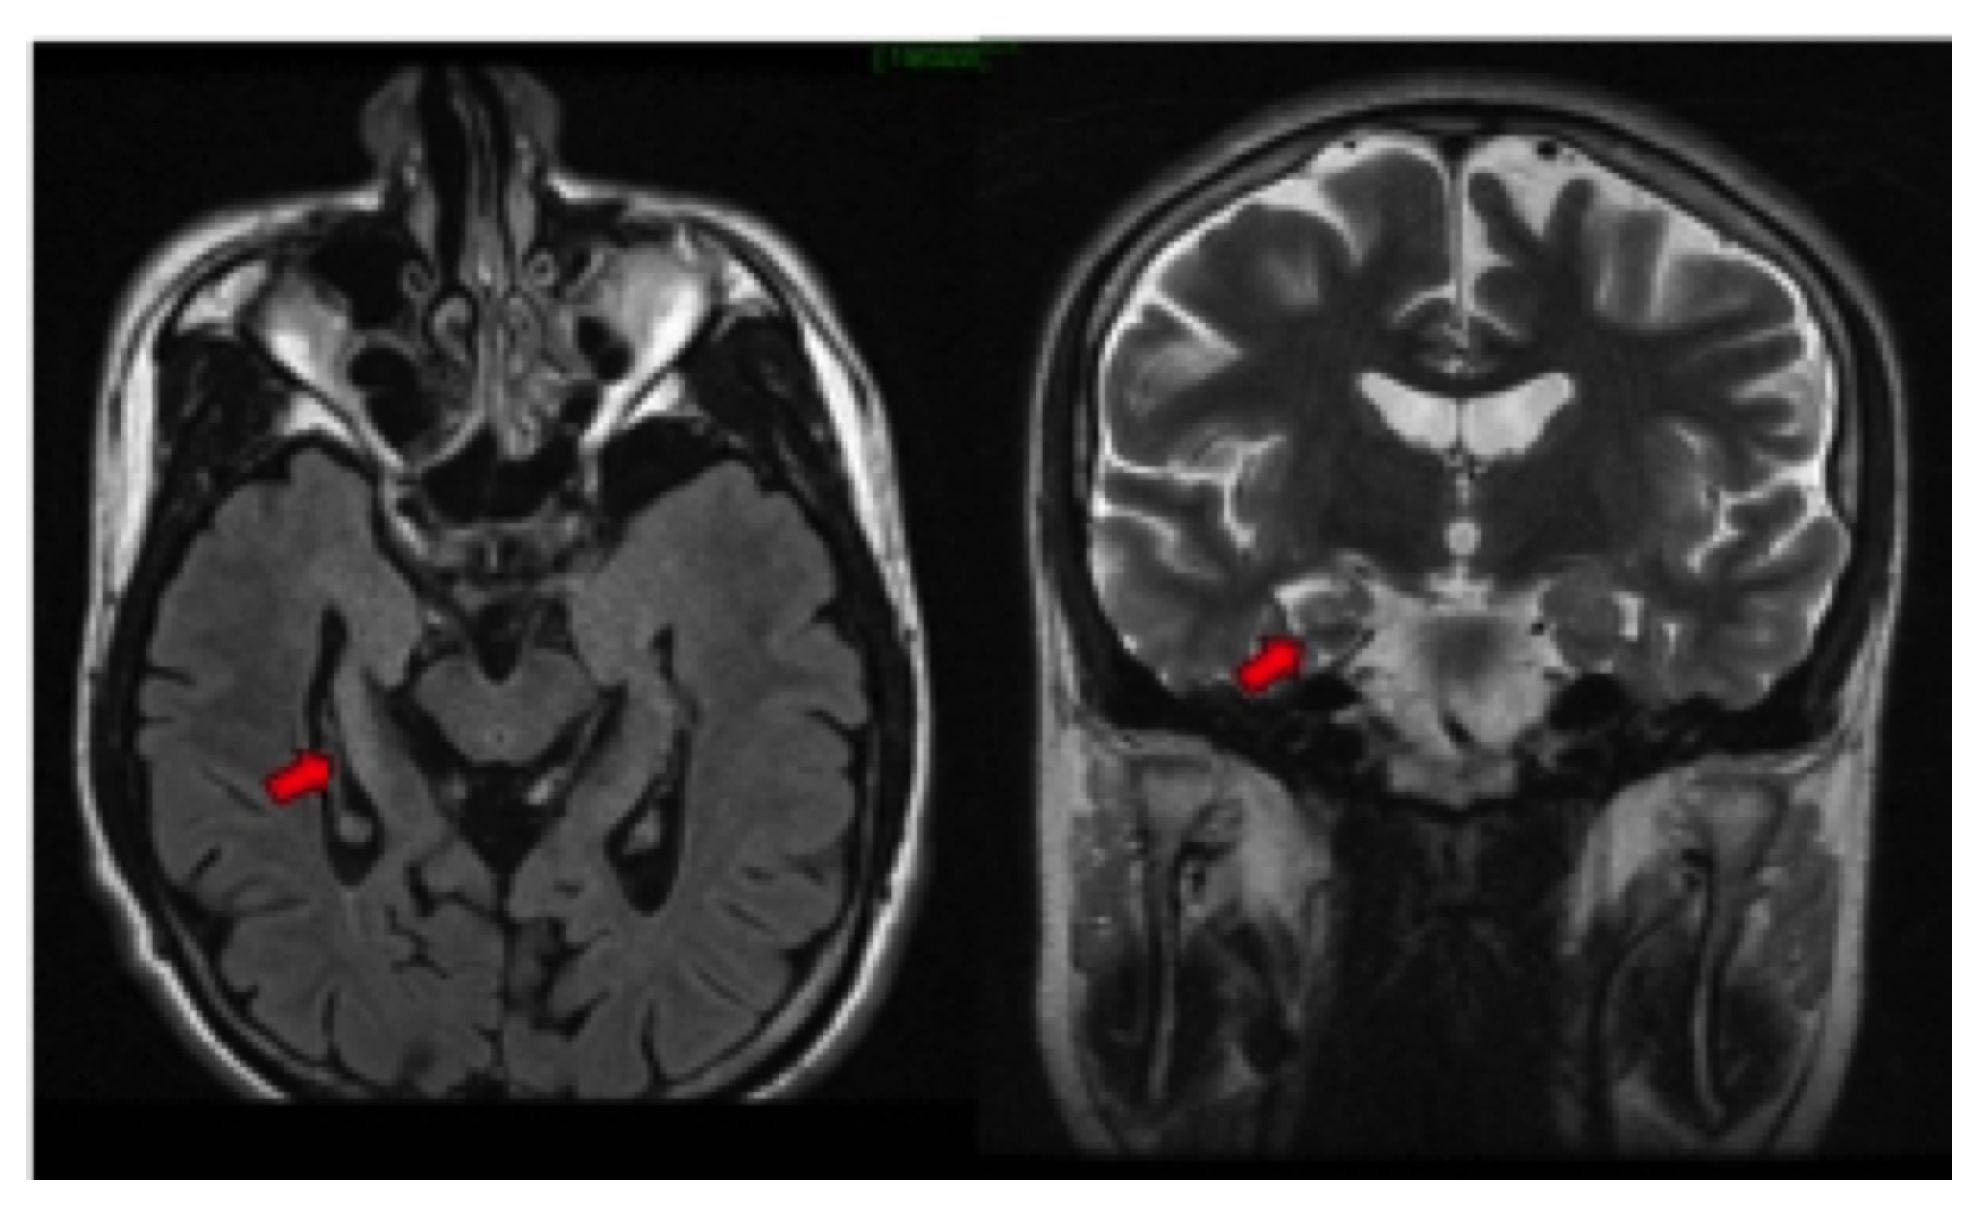

Se reconocen los signos primarios: un hipocampo pequeño o atrófico y un aumento en la intensidad de señal(Figura 2)(29, 30), ipsilaterales al foco epileptógeno, hallazgos que se correlacionan con la pérdida neural y la gliosis (30,31).

Los signos secundarios incluyen pérdida de la arquitectura interna del hipocampo, pérdida de las digitaciones de la cabeza del hipocampo que normalmente contiene dos o tres digitaciones (Figura 3izquierda), dilatación del asta temporal ipsilateral asociada a la atrofia hipocampal, aumento de la intensidad de señal de la amígdala, pérdida de volumen del lóbulo temporal (31), atrofia del cuerpo mamilar (Figura 3derecha), atrofia del fórnix(Figura 4), atrofia del tálamo y atrofia del giro del cíngulo, ipsilateral a la afectación hipocampal (32-34).